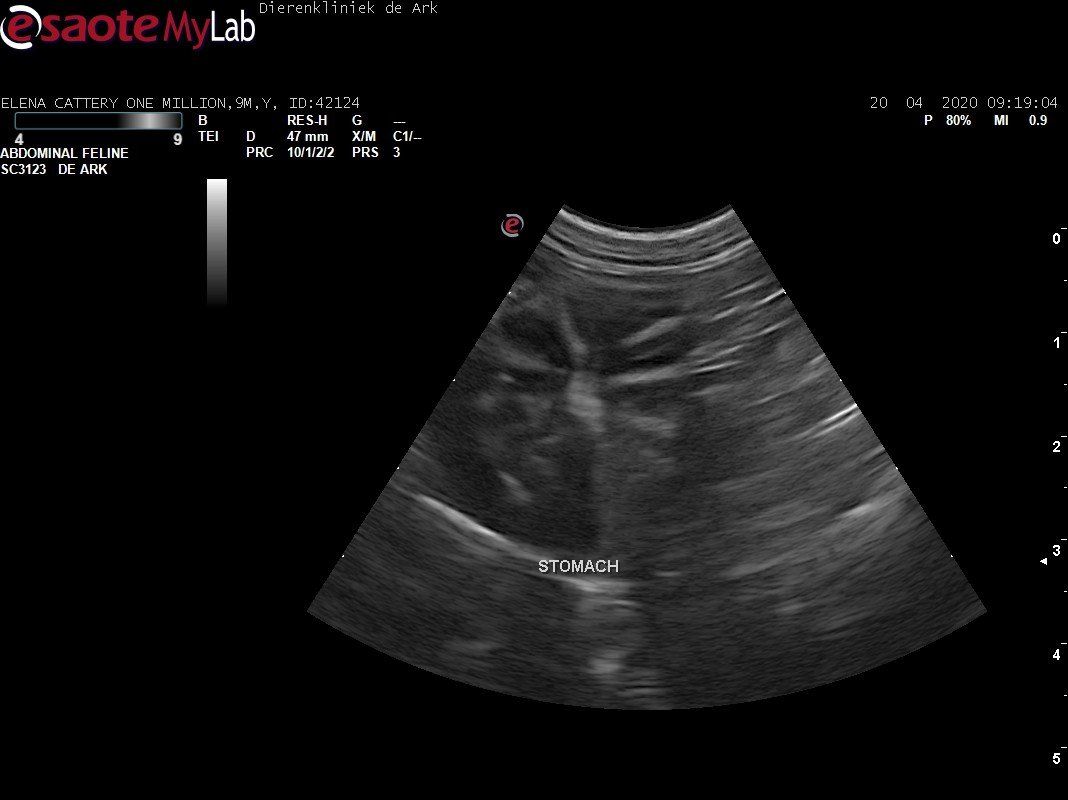

3,200 kg , echo en nieuw bloedonderzoek gedaan wat perfect ging door middel van gapabetine

Voor de garanties en om recht te hebben op medicatie bij herval eist Mutian diverse onderzoeken en controle momenten. Dit zijn bloedonderzoeken maar ook zoals hieronder te zien is echo's. Elana is volledig gecontroleerd op afwijkingen, gelukkig waren de echo's goed.